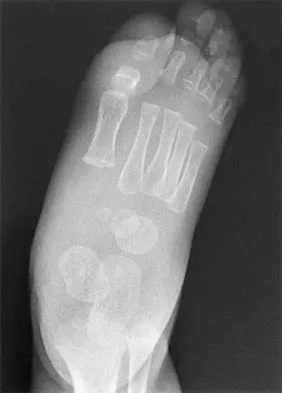

An obese 62-year-old man reports a 10-year history of progressive flatfoot deformity and a 3-month history of a painful callus along the plantar medial midfoot that has not improved with custom shoe wear, pedorthics, and callus care. There is no hindfoot motion, but functional ankle motion remains. He does not have diabetes mellitus. Radiographs are shown in Figures 27a and 27b. What is the best surgical option at this point?

Explanation

The deformity is long-standing, the hindfoot is immobile, and the radiographs reveal severe degenerative arthritis involving the entire hindfoot, severe deformity, and talonavicular dislocation. The "exostosis" responsible for the callus is the talar head; resection would severely destabilize the foot. Degenerative arthritis and fixed deformity preclude lateral column lengthening, medial slide calcaneal osteotomy, and talonavicular arthrodesis. Triple arthrodesis is the only viable option. Johnson JE, Yu JR: Arthrodesis techniques in the management of Stage II and III acquired adult flatfoot deformity. Instr Course Lect 2006;55:531-542.